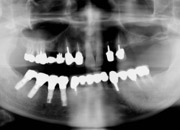

医師が症状を診断し、今後の治療手順に必要な準備を行います。 |

インプラントを埋入して、失われた歯根を修復します。同時に仮歯を装着するため、通常通りの生活ができます。 |

インプラントに最終ブリッジをしっかりと装着します。装着後2〜3回の調整をして完了。 |

従来、無歯顎(歯の無い人)には『総入れ歯』もしくは、片顎8本〜10本のインプラントを埋入しなければならなかったのですが、ポルトガルの Dr.Paulo Malo( パウロ・マロ)によって開発された最新のインプラント治療法のオールオンフォーは4本(もしくは6本まで)のインプラントのみで歯を固定するという画期的な治療方法です。また、オールオンフォーは固定式の仮歯を治療当日に入れられるため、固定が得られれば、治療した即日に噛むことができ、普通の食事が可能です。